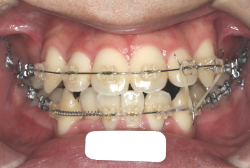

上顎前突

上顎前突(出っ歯)とは上顎が前に出ている状態です。この症状の特徴は、上下の歯並び全体の位置関係が相対的に上顎が優位になっていて、前歯が外に反っているだけでなく奥歯の位置関係も上が前にズレています。さらに凸凹の症状も合併していることがよくあり、上の前歯の見た目を気にして来院する方が多いのですが、実は今言った理由で噛み合わせにも異常があるため、このまま放置すると顎関節症という症状が出ることもあります。

「出っ歯を治したい」という主訴で来院したケースです。診断の結果、「2級1類の上顎前突+軽度叢生」と判明しました。2級というのは、基本的に出っ歯の噛み合わせになっていることを言います。その中でも上の前歯が著しく外に反っているケースを、「1類」といいます。初診時の横向きの写真を見ると、それがはっきり分かります。上の前歯に押されて唇も膨らんで、審美線をかなりオーバーしています(審美線とは、鼻の先端と顎の先端を結ぶ線のことで、この線よりも唇は内側にある方が良いとされています)。

このような症状の場合は、前歯を内側に入れるためにかなり大量の隙間を必要とします。通常は上下左右の小臼歯を抜歯させていただくのが正解です。治療後は歯の角度が正しくなっただけでなく、唇の審美性が大幅に改善しました。もちろん噛み合わせ的にも正しい状態が確立しています。